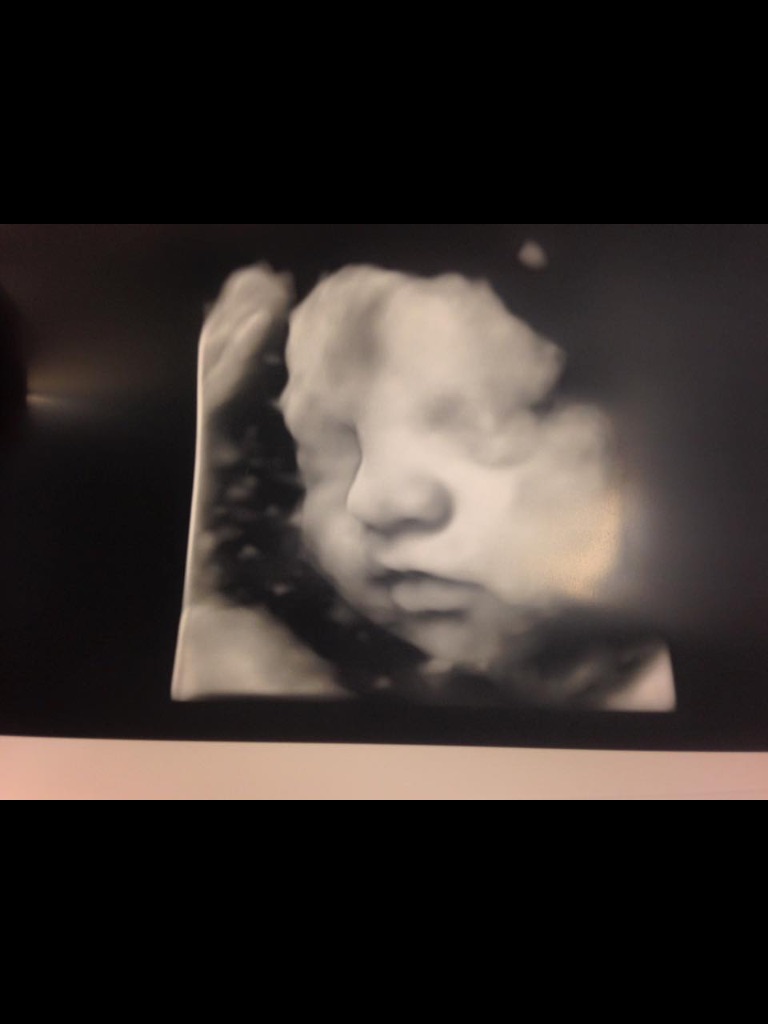

Had an ultrasound yesterday at 36wks to check baby's size since my belly is measuring 41+cm. Found out our LO has several ovarian cysts four cm big. As a result I have polyhydromnios (excess amniotic fluid). Weekly appts now include an ultrasound and extra fetal monitoring. No talk of induction but I assume having excess fluid could make for an early arrival. Anyone heard of this scenario before? Got awesome pics of her though!